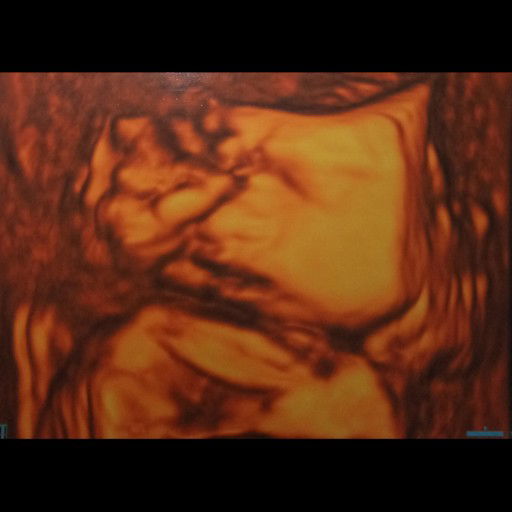

Berapa ya jumlahnya? ๐Ÿค”

Menangkan Shopeepay senilai total Rp 250.000 untuk 5 orang pemenang beruntung! Hanya berlaku dari 23 - 26 Juli 2022. Oh ya, selamat Hari Anak Nasional!